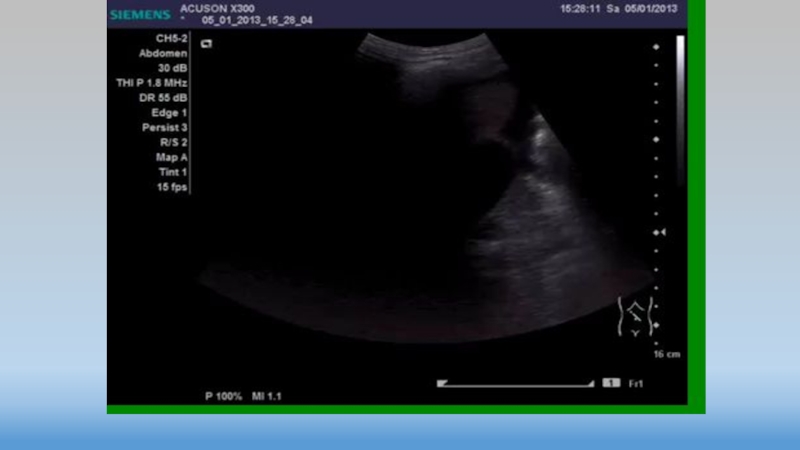

Слайд 21Точки 5-6

Точки 5-6

Слайд 22Точки 5-6